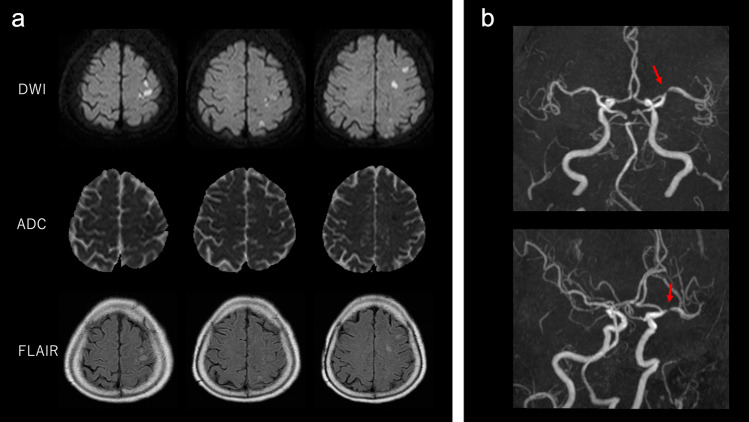

Fig. 1.

Magnetic resonance imaging and magnetic resonance angiography (MRA) findings. a Diffusion-weighted imaging (DWI), apparent diffusion coefficient (ADC), and fluid-attenuated inversion recovery (FLAIR) images. Brain DWI and FLAIR images show multiple acute cerebral infarctions in the territory of the middle cerebral artery. b MRA revealed left middle cerebral artery (M1) stenosis (red arrow)

When the patient arrived at the hospital, Glasgow Coma Scale (GCS) was 6/15, with right conjugate deviation; pulse was 120 beats/minute; blood pressure was 90/60 mmHg; respiratory rate was 30 breaths/minute, with Kussmaul breathing; blood oxygen saturation was unmeasurable by pulse oximeter; and body temperature was 38.2 °C. Laboratory investigation revealed a metabolic acidosis with arterial blood pH of 6.85, pO2 114.6 mmHg, and pCO2 25.7 mmHg with oxygen inhalation (Table 1). Serum glucose level was 683 mg/dL and total ketone body level was 7,820 μmol/L. White blood cells (WBCs) were 15,000/μL, segmented neutrophils were 72.6%, and C-reactive protein level was 37.61 mg/dL. Urinalysis showed no findings suggestive of a urinary tract infection. Rapid urinary antigen detection kit for Streptococcus pneumoniae and nasopharyngeal SARS-CoV-2 PCR were negative. Brain–chest–abdomen computed tomography (CT) was performed, but there was no lesion that could be the focus of infection. Blood cultures and urine cultures showed no significant bacterial growth. The patient was admitted to the intensive care unit with a diagnosis of DKA. She was intubated and ventilated because of her deteriorated respiratory condition. We started intravenous insulin infusion (0.1 units/kg/h), intravenous fluid infusion, and empirical antibiotic treatment. The average total daily insulin dose was 102 units/day during day 2 to day 6 after the hospitalization. Although her blood glucose levels were normalized on day 2, her level of consciousness did not improve. To rule out the possibility of meningitis, a lumber puncture was performed, but cerebrospinal fluid analysis was normal. Multiple subacute cerebral infarctions in the territory of the left middle cerebral artery was confirmed by brain magnetic resonance (MR) imaging (Fig. 1). MR angiography presented left middle cerebral artery M1 stenosis suggestive of atherothrombotic stroke (Fig. 1), and antiplatelet treatment was initiated. The patient’s GCS and serum C-reactive protein levels gradually improved within 1 week, though mild right hemiplegia still remained. After being extubated on day 11, oral feeding was initiated. She underwent extensive neurorehabilitation until she regained a power grade of 4/5 in right limbs, and finally she was discharged from the hospital to her home on the 34th day after admission.